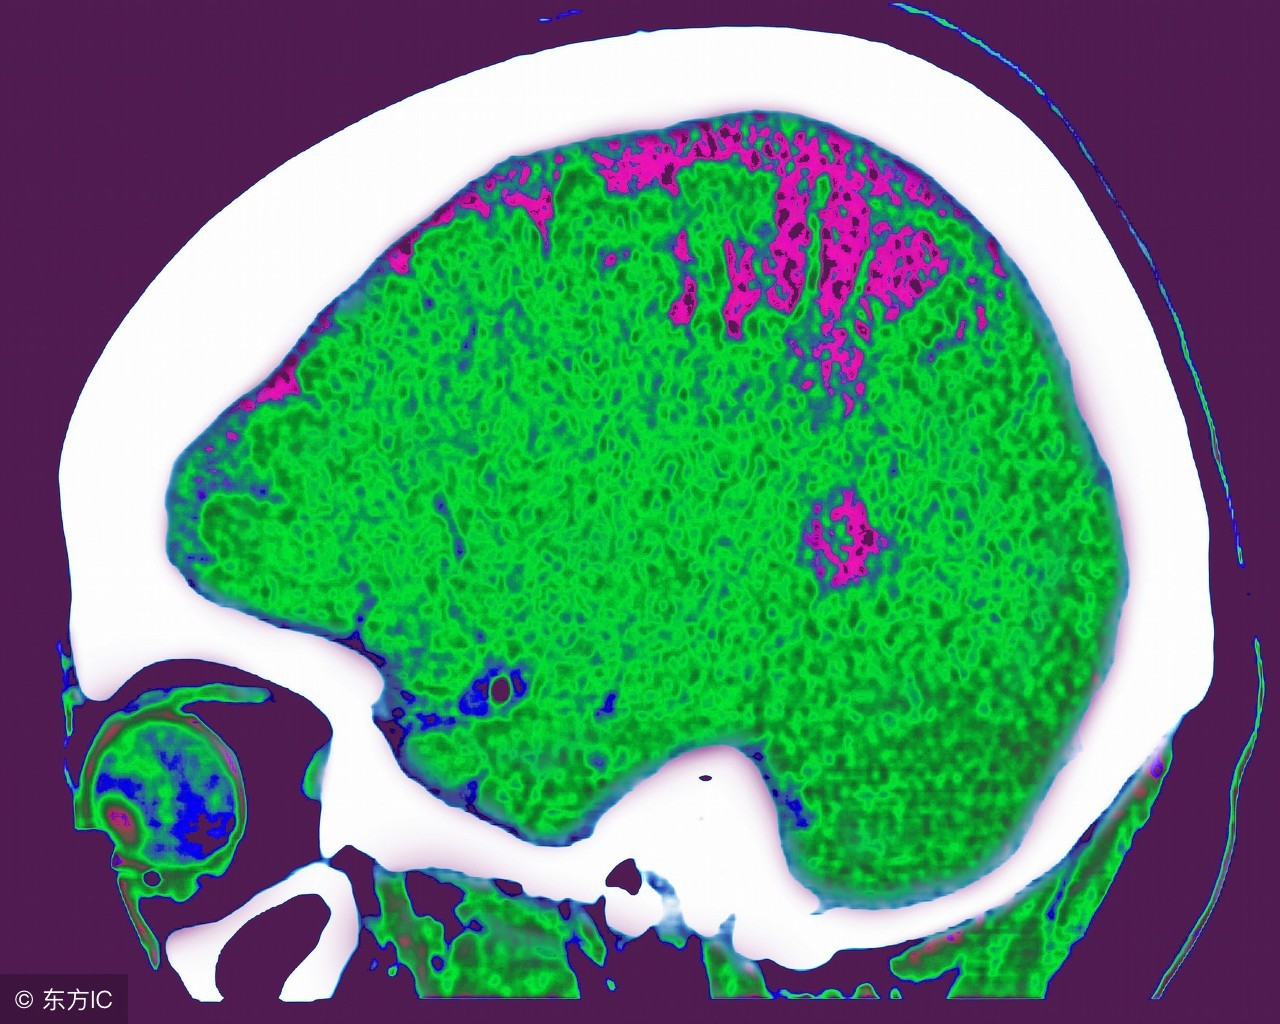

小脑萎缩就会导致患者在行为方面或者是语言上跟不上节奏,这会给患者的生活带来极大的影响,所以说我们建议哪些小脑萎缩的患者应该去医院及时的去接受正规治疗。小脑萎缩的这种疾病主要的发病人群是身体已经开始出现退化了的老年人的身上,它是会让老年人开始失去大脑当中的记忆,我们应该理解和帮助他们积极的去参与小脑萎缩的治疗。